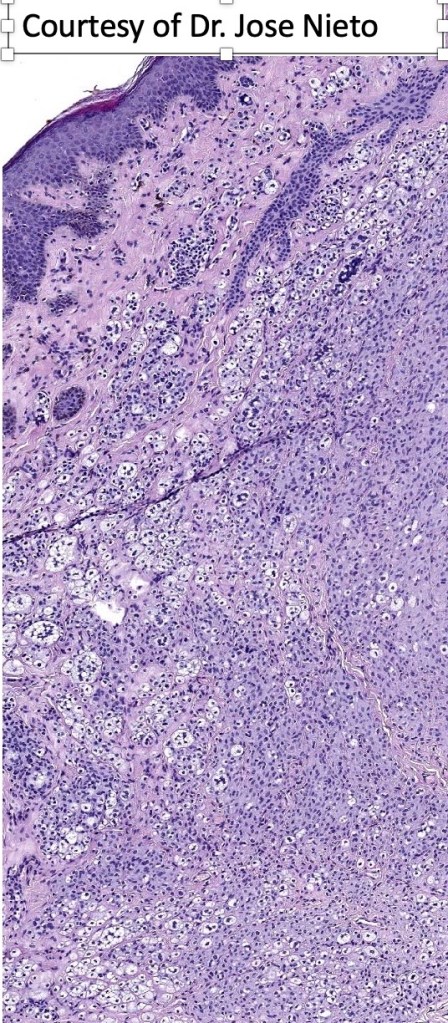

Histological features

.Balloon cell change is most often seen in banal melanocytic nevi but it has also rarely been described in cellular blue nevus, dysplastic nevus, combined nevus, halo nevus & Spitz nevus. Lesions with <50% of balloon cells are sometimes described as nevi with balloon cells. Nevi with >50% balloon cells are described as balloon cell nevus.

.Balloon cell nevs genrally has uniform, hyperchromatic nuceli (as opposed to the vesicular nuclei with prominent nucleoli) seen in melanoma. Mitoses are absent.(In my experience, balloon cell melanoma is more common than balloon cell nevus).

. In some balloon cell nevi, the microvesicles may result in nuclear scalloping reminiscent of a sebaceous tumor. In cases where there is real doubt, immunohistochemistry (S100), SOX10) will resolve the problem.

The importance of the entity is that it must always be distinguished from balloon cell melanoma. All cases should be scrutinized very carefully for pleomorphism and mitotic activiy before rendering a diagnosis of balloon cell nevus.